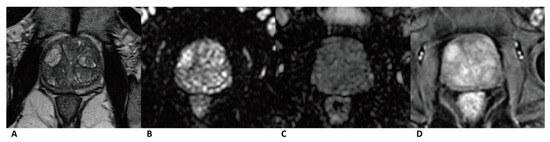

Figure 4. Case of benign prostate hyperplasia. Male, 64 years old, benign prostate hyperplasia. T2WI showed multiple slightly hypo/hyper-intense encapsulated nodules in TZ (A). The lesion was isointense on the DWI and ADC map (B,C). A diffuse popcorn-like enhancement was seen on the DCE and was assessed as negative (D). It was finally assessed as a category 2, indicating that it had a low cancer risk according to PI-RADS v2, pa PI-RADS v2, and biparametric MRI protocols.

In total, 19 (17.4%) out of 109 cases of benign lesions in TZ were misdiagnosed as cancer by upgrading the standard in PA PI-RADS v2. The specificity and accuracy of PA PI-RADS v2 (77.98% and 81.97%) for TZ lesions were lower than those of PI-RADS v2/biparametric MRI (95.41% and 93.54%). The high false positive rate could be attributed to the changes in upgrading the standard from category 3 to 4 in PA PI-RADS v2. Moreover, 14 misdiagnosed cases were upgraded by the positive DCE result, wherein the inter-reader agreement was only moderate (k = 0.408). The assessment based on the DCE image was, to some extent, subjective and controversial, which led to lower specificity and accuracy. Interpreting images of benign lesions is complicated, and it is sometimes hard to differentiate them from prostate cancer based on a DCE image [27]. Encapsulated swirled or popcorn-like enhancement patterns (Figure 3) caused by hypervascularity in prostate hyperplasia were defined as negative in PA PI-RADS v2 and could be used as a sign for diagnosing prostate hyperplasia [8]. However, this enhancement pattern was defined as positive in PI-RADS v2. Further studies are needed to testify for this standard in PA PI-RADS v2 and refine its details to help practitioners better understand the standard. No difference was found in the AUC of the ROC curve for the two protocols that diagnosed TZ lesions, although prior research found a higher specificity and accuracy for PI-RADS v2 [28,29,30,31]. Whether DCE could be used in microvascular anatomy and functional evaluation to improve the detection specificity and accuracy for TZ lesions needs further study [32,33,34,35].